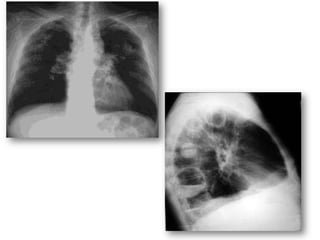

• Stade V: stade séquellaire

• Aspect radiologique variable selon le degré de

l’évacuation du kyste:

- Image d’incarcération des membranes .

- Image de membrane pelotonnée

- Image en cocarde , en grelot

Evolution du kyste chez l’hôte

• Stade VI:Calcification :

- dépôts calcaires sur adventice , signes

radiologiques caractéristiques»image en

coquille d’œuf »

- La calcification ne traduit pas la dégénérescence

du kyste.

- Exceptionnelle au niveau des poumons